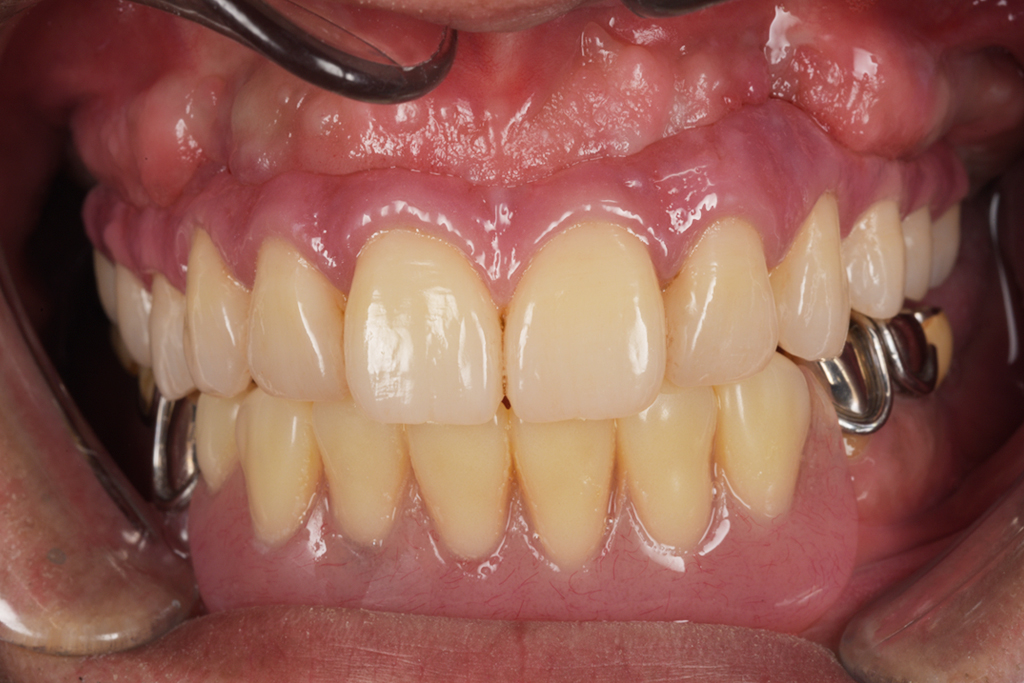

Hさまは今まで歯医者が嫌いで行かないでそのまま放置していました。タバコもヘビースモーカーと自分で言うくらいの量を吸っていたそうです。

放置していたらどんどん歯がボロボロになっていき、噛めないことと痛みがあるのでどうしたらいいかと、重い腰を上げてきてくださいました。

今回は噛めることと見た目の改善を目的として上顎はダメな部分は抜歯をし、インプラントを入れました。

Hさまのインプラント治療は1年かかりました。理由としてはヘビースモーカーのためインプラントが骨と定着しなかった部分があったため何本か抜けてしまったりし、再度インプラントを入れ直したり等したためです。

タバコを止めることがストレスになるとのことでした。インプラント治療には禁煙は必須ですがストレスのが強いのであれば、インプラントが定着せず抜けてしまう可能性は増えますが、辛抱強く行えばインプラントはいつかは定着すると私も勉強させられました。

ヘビースモーカーでも治療が可能と今では言える様になりました。(歯科医師としては言ってはいけないと思いますが・・・)

現在では硬いものもかめてやってよかったと言われて私は満足しかありません。